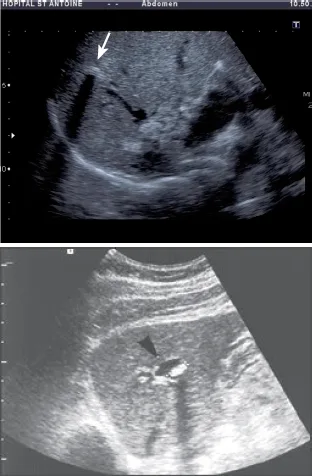

3) C’est la réalisation d’une échographie par un opérateur sensibilisé à la recherche des signes évocateurs qui est, en pratique, le moyen le plus pertinent pour confirmer le diagnostic. En effet, chez les patients atteints de syndrome LPAC avec mutation ABCB4, cette échographie experte révèle des anomalies typiques dans 88 à 95 % des cas (4, étude LPANGH). Cette haute pertinence diagnostique est également retrouvée en cas de syndrome LPAC sans mutation ABCB4 [4]. Le diagnostic radiologique repose sur la mise en évidence de spots hyper-échogènes intra-hépatiques responsables d’images en queue de comète de topographie compatible avec des dépôts de microcristaux le long de l’arbre biliaire (Fig. 2). Il peut aussi s’agir de sludge, d’une micro-lithiase intra-hépatique ou de macro-calculs avec cône d’ombre (Fig. 3). À l’inverse, une échographie pratiquée par un radiologue non expert et non averti du diagnostic supposé de syndrome LPAC (il s’agit le plus souvent d’échographies pratiquées en urgence devant des symptômes biliaires) ne décrira les signes de la maladie que dans 5 % des cas de syndrome LPAC (étude LPANGH).

Dans à peu près 5 % des cas, le syndrome LPAC est responsable d’une dilatation sacculaire des voies biliaires intra-hépatiques qui moulent des macro-calculs cholestéroliques sans sténose biliaire sous-jacente (Fig. 5) [8]. Le diagnostic différentiel à évoquer est la dilatation primitive congénitale des voies biliaires intra hépatiques (maladie de Caroli diffuse ou dilatation primitive localisée à un lobe ou un segment).